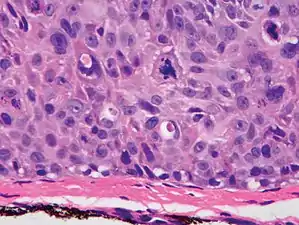

Degree of differentiation

Poorly differentiated, where attempts at keratinization are often no longer evident. This is a clear-cell squamous-cell carcinoma. The dysplastic cells infiltrated cords through the dermis. Poorly differentiated cSCC has greatly enlarged pleomorphic nuclei showing a high degree of atypia and frequent mitoses.[12]

Poorly differentiated clear-cell squamous-cell carcinoma. For this type of cSCC, immunostains will likely be required to classify it unless other areas of the tumor show obvious squamous-cell features such as seen here (arrow).